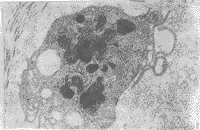

图2 EC结构完整,核质清晰,其下纤维细胞形态规整 ×6 000

图3 胶原纤维暴露、紊乱,无EC生长 ×1 000

2.2 扫描及透射电镜检查结果 Ⅱ组见EC附着生长,细胞形态不一,其下基膜组织表面完整光滑。EC结构基本完整,核质清晰,其下可见基膜组织层次清晰,纤维细胞形态规整,胞膜核膜完整,核染质分布正常。胶原纤维排列整齐,明暗带清晰(图1,2)。

Ⅲ组瓣叶表面纤维组织暴露,无EC附着,表面粗糙、紊乱,局部有断裂、缺失现象。未发现结构完整的细胞(图3,4)。